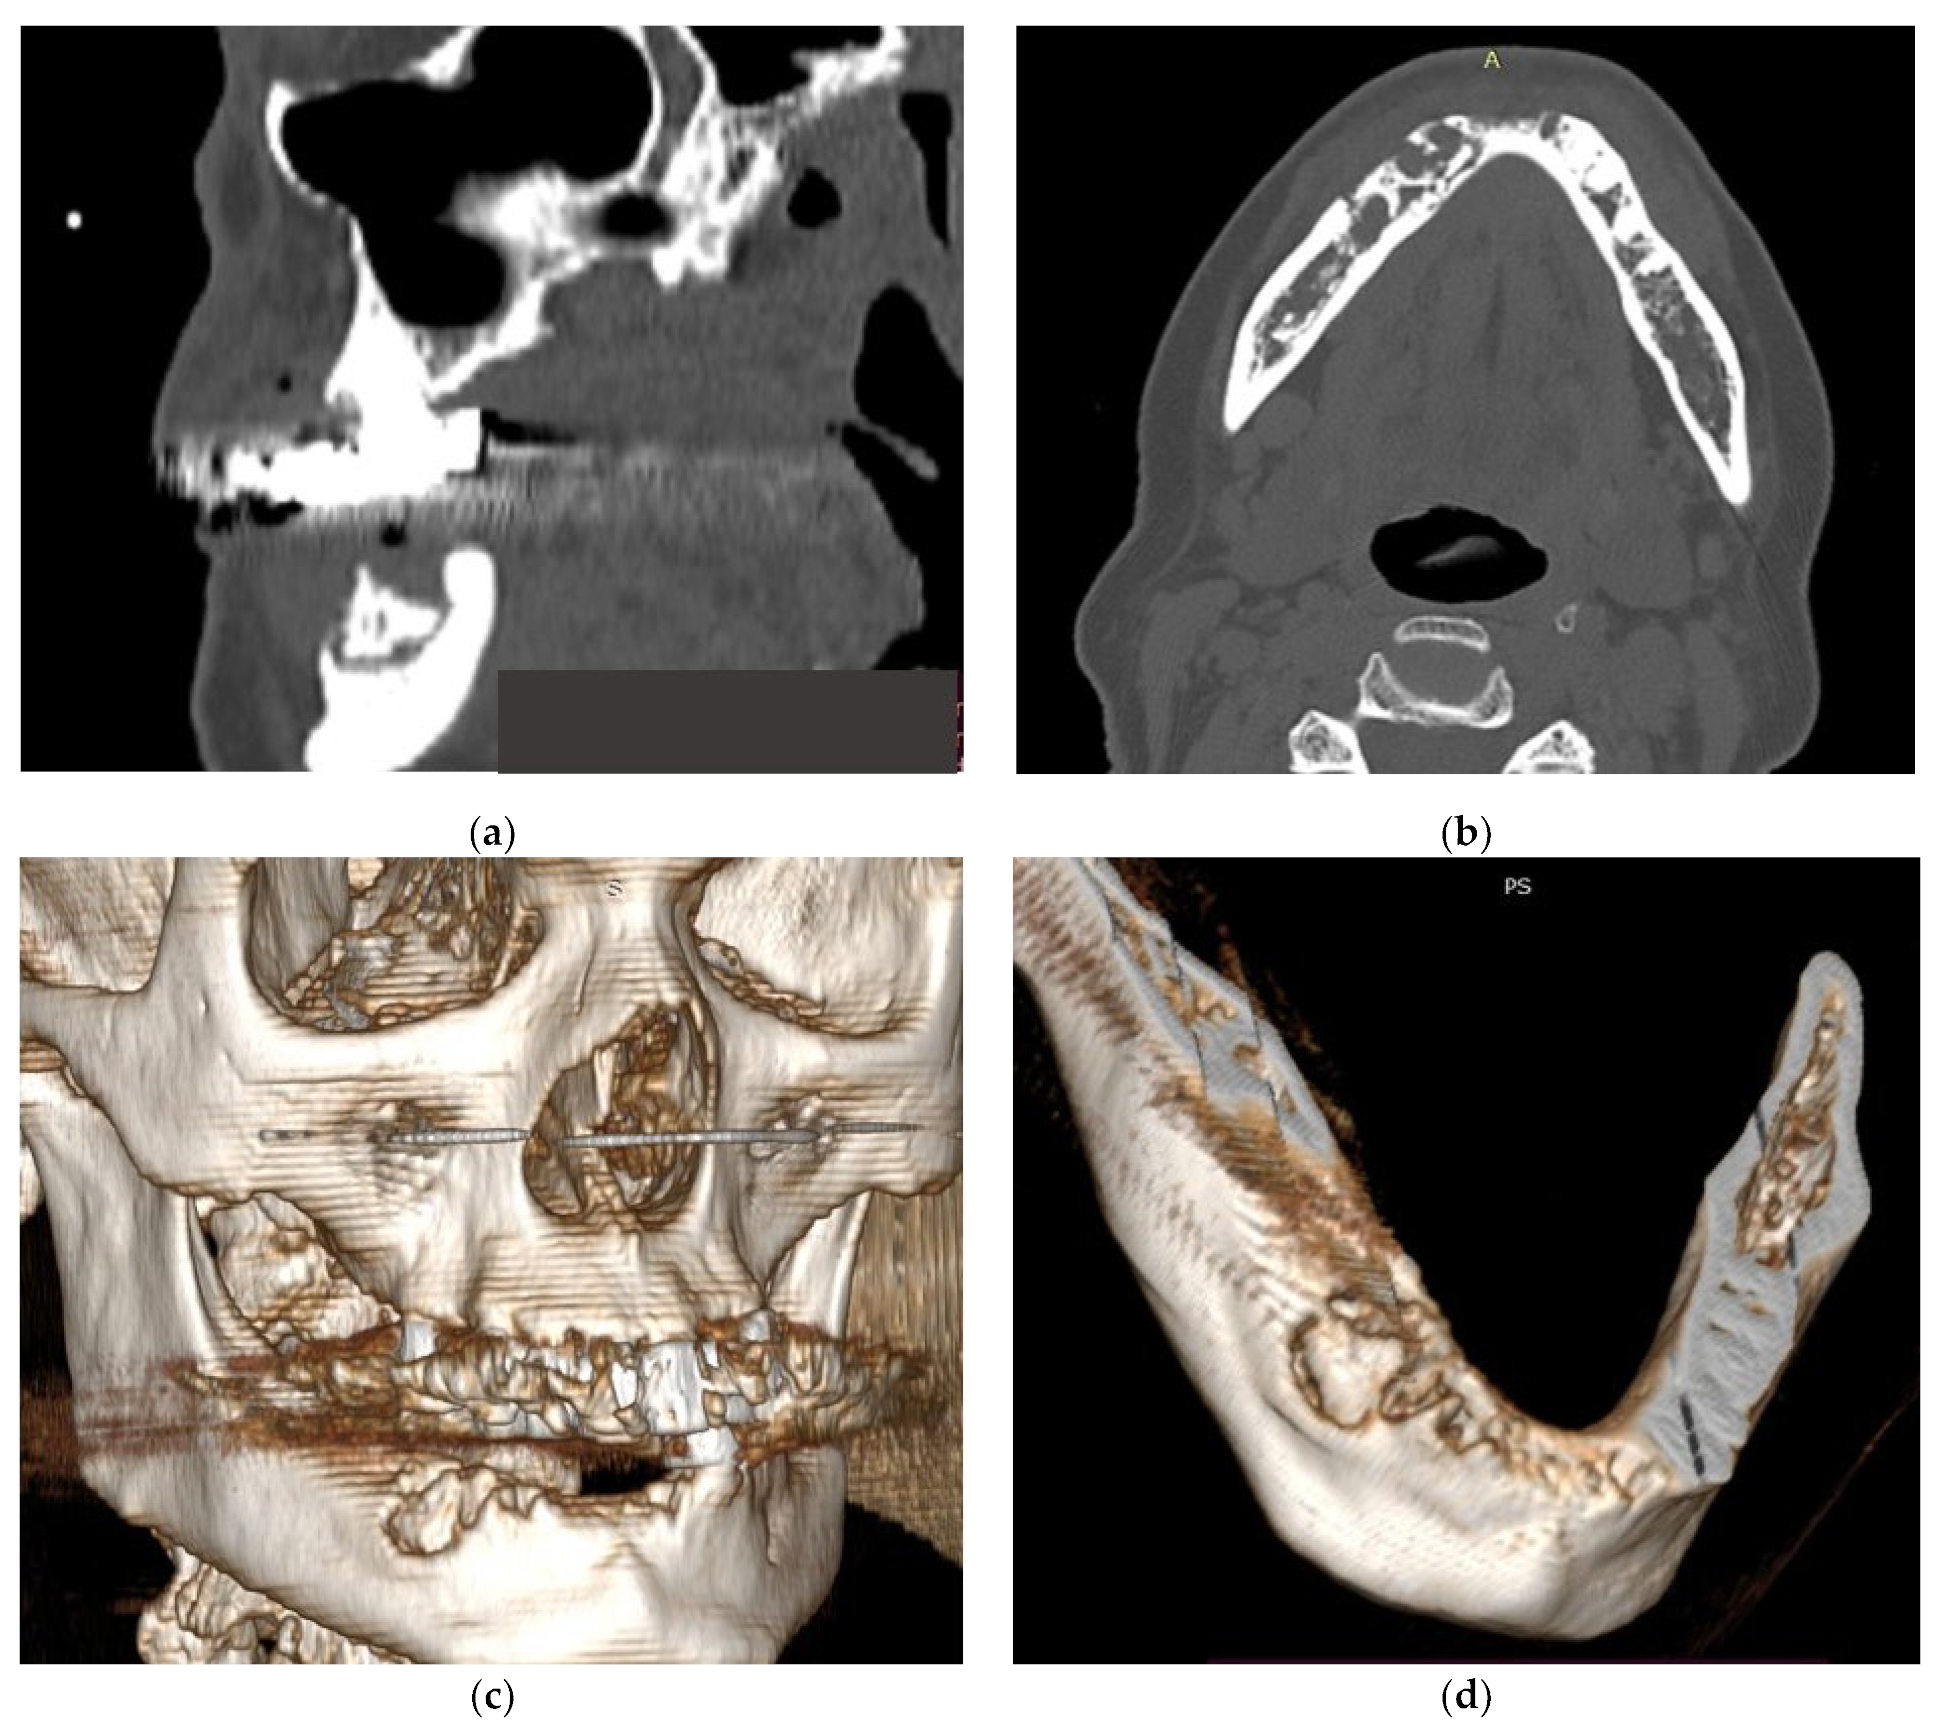

All patients were diagnosed with cancer and bone metastasis and developed MRONJ (Figure 1). Patients reported local radiating pain in both jaws, with oral dysfunction (mostly with an altered masticatory function or physiognomic alterations for patients with MRONJ in the frontal area of the jaws) (Figure 2). One patient complained of paresthesia in the lower jaw.

Figure 1.

(a–d) CT aspects of patients with MRONJ.